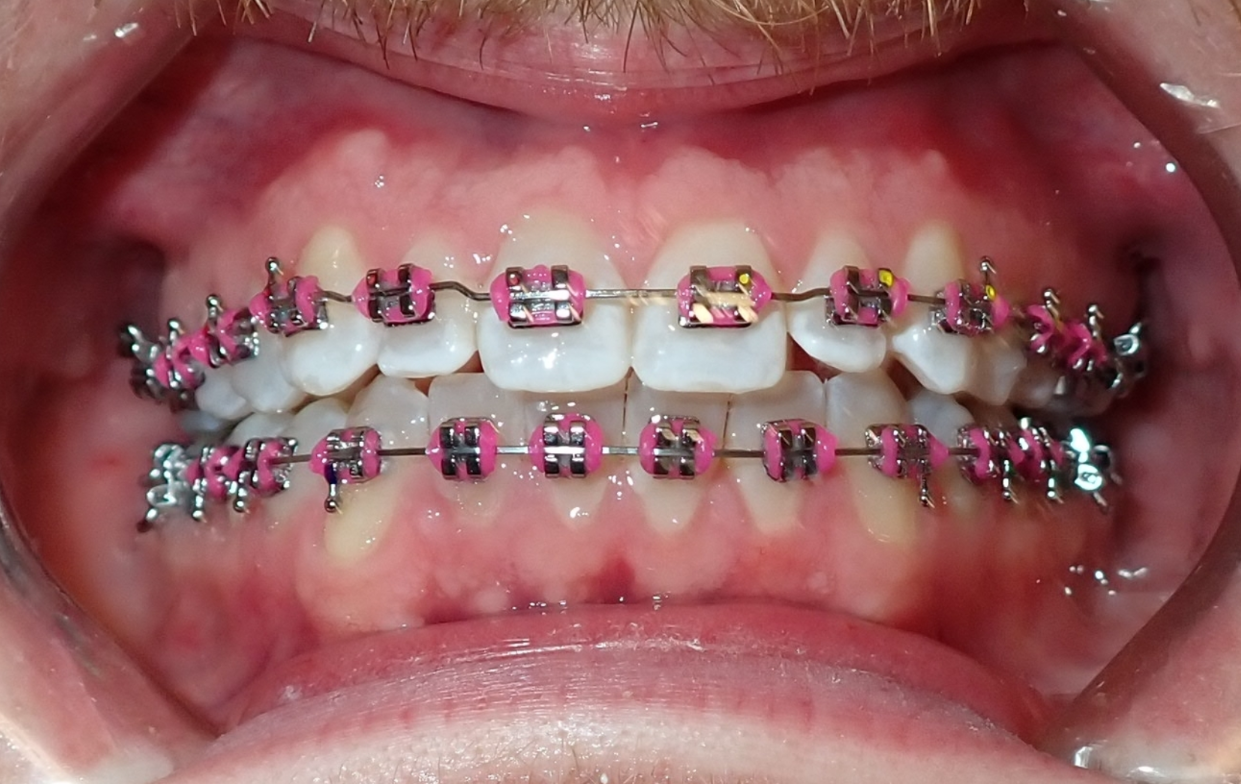

Ortodoncia para adolescentes

¡La vida de un adolescente es muy ocupada! Ofrecemos planes de tratamiento que se adaptan a tu horario y estilo de vida, y que acompañan tus actividades, deportes, selfies y todo lo demás.

Close-up of a person's mouth showing braces on the upper and lower teeth, with some braces having pink bands.